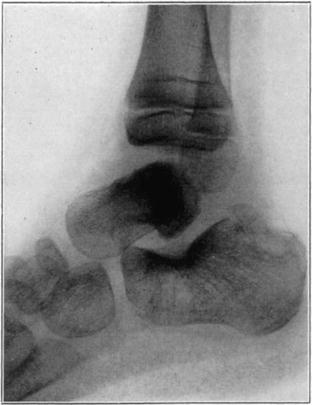

Necrosis of Os Calcis

In fracture of the neck of the os calcis the body may rarely have so much of its blood supply cut off that it undergoes extensive necrosis. Its subsequent history is analagous to that of a necrotic proximal fragment in intracapsular fracture of the neck of the femur. If bony union between the fragments follows, the necrotic body will be invaded gradually by blood vessels, fibrous, osteogenic, and myelogenous tissue, and a gradual replacement of the necrotic by living elements will be brought about. The replacement may be incomplete and the necrotic portion located farthest from the fracture may be broken down by weight-bearing before the ingrowing tissue reaches it, thereby leading to deformity and permanent derangement of the bone.

The following cases are illustrative of this condition.

Case 2. Seventy-four days after fracture of neck of astragalus, posterior dislocation of body, and reduction by operation. Body necrotic and retained normal density. Atrophy of disuse of other bones. Bony union of fracture.

Case 2. One hundred and sixty days after fracture. Body slightly reduced in density near fracture due to invasion from neck.

Case 3. Fresh fracture of neck of astragalus and chip off superior and posterior portion of os calcis.

Case 3. Two hundred and seventy-four days after injury. Fracture of astragalus united. Superior and posterior part of body broken down and irregular while remaining portion dense and transformed. Indicative of necrosis of body with secondary changes.

Case 3. Eighteen months after injury, showing a defective but gradually reforming articular portion of the body of the astragalus.

The blood supply of the astragalus is derived mainly from a branch of the arteria dorsalis pedis which traverses the sinus tarsi lateral to the neck and breaks up to enter the bone near the junction of the neck and body along the lateral and inferior surfaces. There are very small branches entering the bone mesially and posteriorly at points of ligamentous and capsular attachments. Apparently when there is a fracture along the junction of body and neck the important vessels to the body are interrupted and there may be insufficient circulation through the remaining vessels, so that aseptic necrosis of a large part or all of the fragment follows. It is evident from the partial collapse which occurred in Case 3 that when necrosis of the body is diagnosed, the limb should be protected from weight-bearing for at least several months,—until union, revascularization, and transformation of necrotic area has been largely brought about. It seems probable that some of the bad results that have been reported in fracture of the neck of the astragalus, either united or ununited, have been due to overlooked aseptic necrosis of the body.